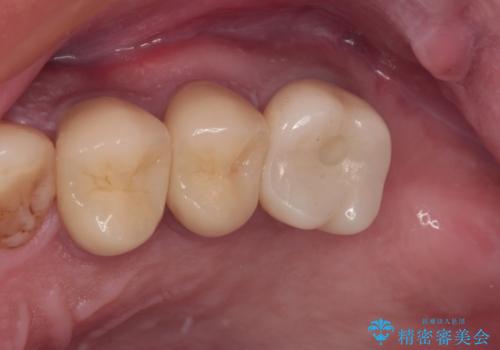

- ぼろぼろになった奥歯を治療したいとのことで来院された患者様です。

重度の歯周病と歯列不正が認められたため、歯周病治療やインプラントによる咬合回復を行った後に矯正治療を実施し、最終的にオールセラミッククラウンに補綴することとしました。

歯列不正などによるプラークコントロールの不良が治療を困難なものとしましたが、矯正治療後は歯肉の状態も落ち着き、安定した状態でオールセラミッククラウンの補綴を行うことができました。